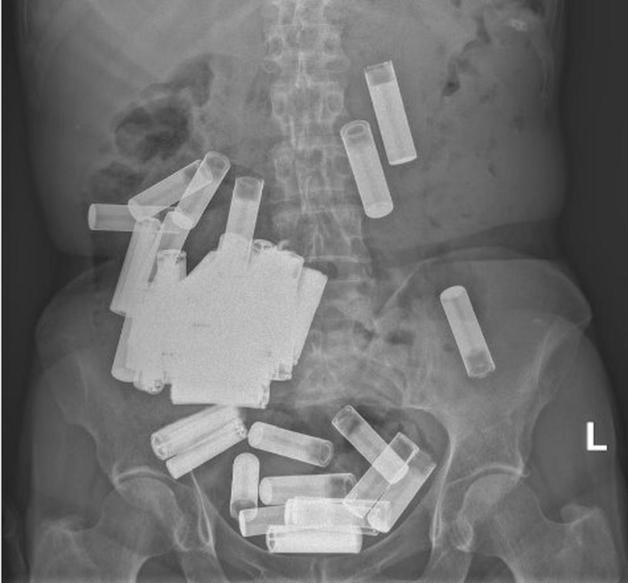

건전지 수십 개를 삼킨 여성의 복부 엑스레이 사진. (아이리시 인디펜던트) © 뉴스1

15일(현지시간) 아이리시 인디펜던트, 아이리시타임스 등의 보도에 따르면 66세의 한 여성이 더블린에 있는 세인트빈센트병원에서 배에 들어있는 50개의 배터리 제거 수술을 받았다.

이번 달 아일랜드의 공식 의학저널은 여성의 복부 엑스레이 사진을 공개해 사건에 대해 자세히 설명했다.

여성의 위는 건전지의 무게로 인해 치골까지 늘어난 상태였다. 의료진은 결국 개복술을 시행하기로 결정, 위 절제술을 통해 위에서 46개, 대장에서 4개 총 50개의 배터리를 빼냈다.